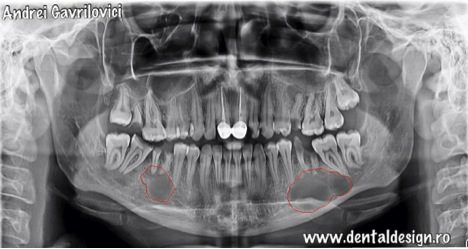

După aceea nu a mai fost la dentist să-și facă extracțiile de frică să nu mai treacă prin aceeași experiența dureroasă. Timpul a trecut, infecția s-a făcut din ce în ce mai mare în os, apărând un chist în dreptul primului molar inferior din partea stânga și un altul în dreptul primului molar inferior din partea dreaptă, respectiv cei doi dinți la care s-a încercat efectuarea extracțiilor.

Chistul de pe partea dreaptă este de formă ovală, având diametrul mare de aproximativ 3 centimetri și diametrul mic de 1,5 centimetri, iar chistul de pe partea stângă apare pe radiografie de forma rotundă cu un diametru de 2cm.

Atunci când pacienta a hotărât că nu mai poate sta cu acele resturi dentare în gura, s-a prezentat din nou la medicul dentist, pentru a-și extrage acele rădăcini. Medicul dentist i-a recomandat să facă o radiografie panoramică înainte de extractii și așa a observat prezența a două chisturi la nivelul rădăcinilor primilor molari inferiori, aceiași dinți care au încercat să fie scoși în urmă cu câțiva ani.